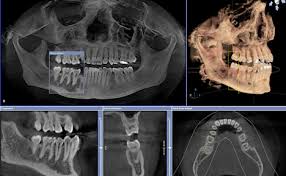

Global Dental CBCT Market: Product Segment Analysis

- Large FOV

- Medium FOV

- Other (Small FOV, Custom Super FOV models, etc.)